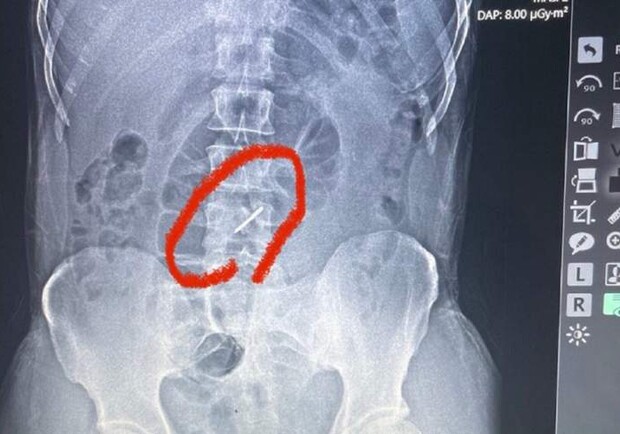

Лейтенант ВС РФ Леонид Пигин в течение полутора суток продолжал борьбу с врагом из подбитого БТР, несмотря на то, что получил тяжелейшее ранение. Об этом боец рассказал телеканалу "Звезда" ukraina.ru »